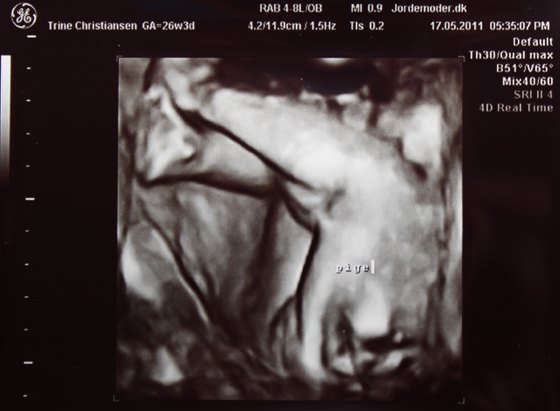

Vi var til en kønscanning i dag

og der var ingen tvivl om at det er en lille fin prinsesse der gemmer sig derinde i hulen

eller lille er måske så eget sagt.. heh.. Der blev selvfølgelig taget lidt forskellig mål og lavet et skøn på vægten, som lyder på Ca. 913g.

Og her kommer der så et par billeder

To hvor man kan se hovedet og et hvor man kan se kønnet (og det er virkelig ingen tvivl)